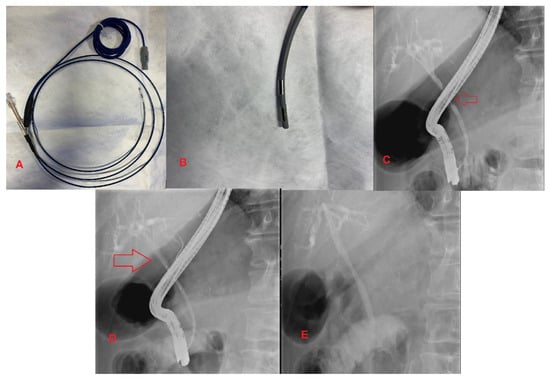

3.4. Endobiliary Radiofrequency Ablation (RFA)

- Inoue, T.; Ito, K.; Yoneda, M. Novel balloon catheter-based endobiliary radiofrequency ablation system: An ex-vivo experimental study. Dig. Endosc. 2020. [Google Scholar] [CrossRef] [PubMed]